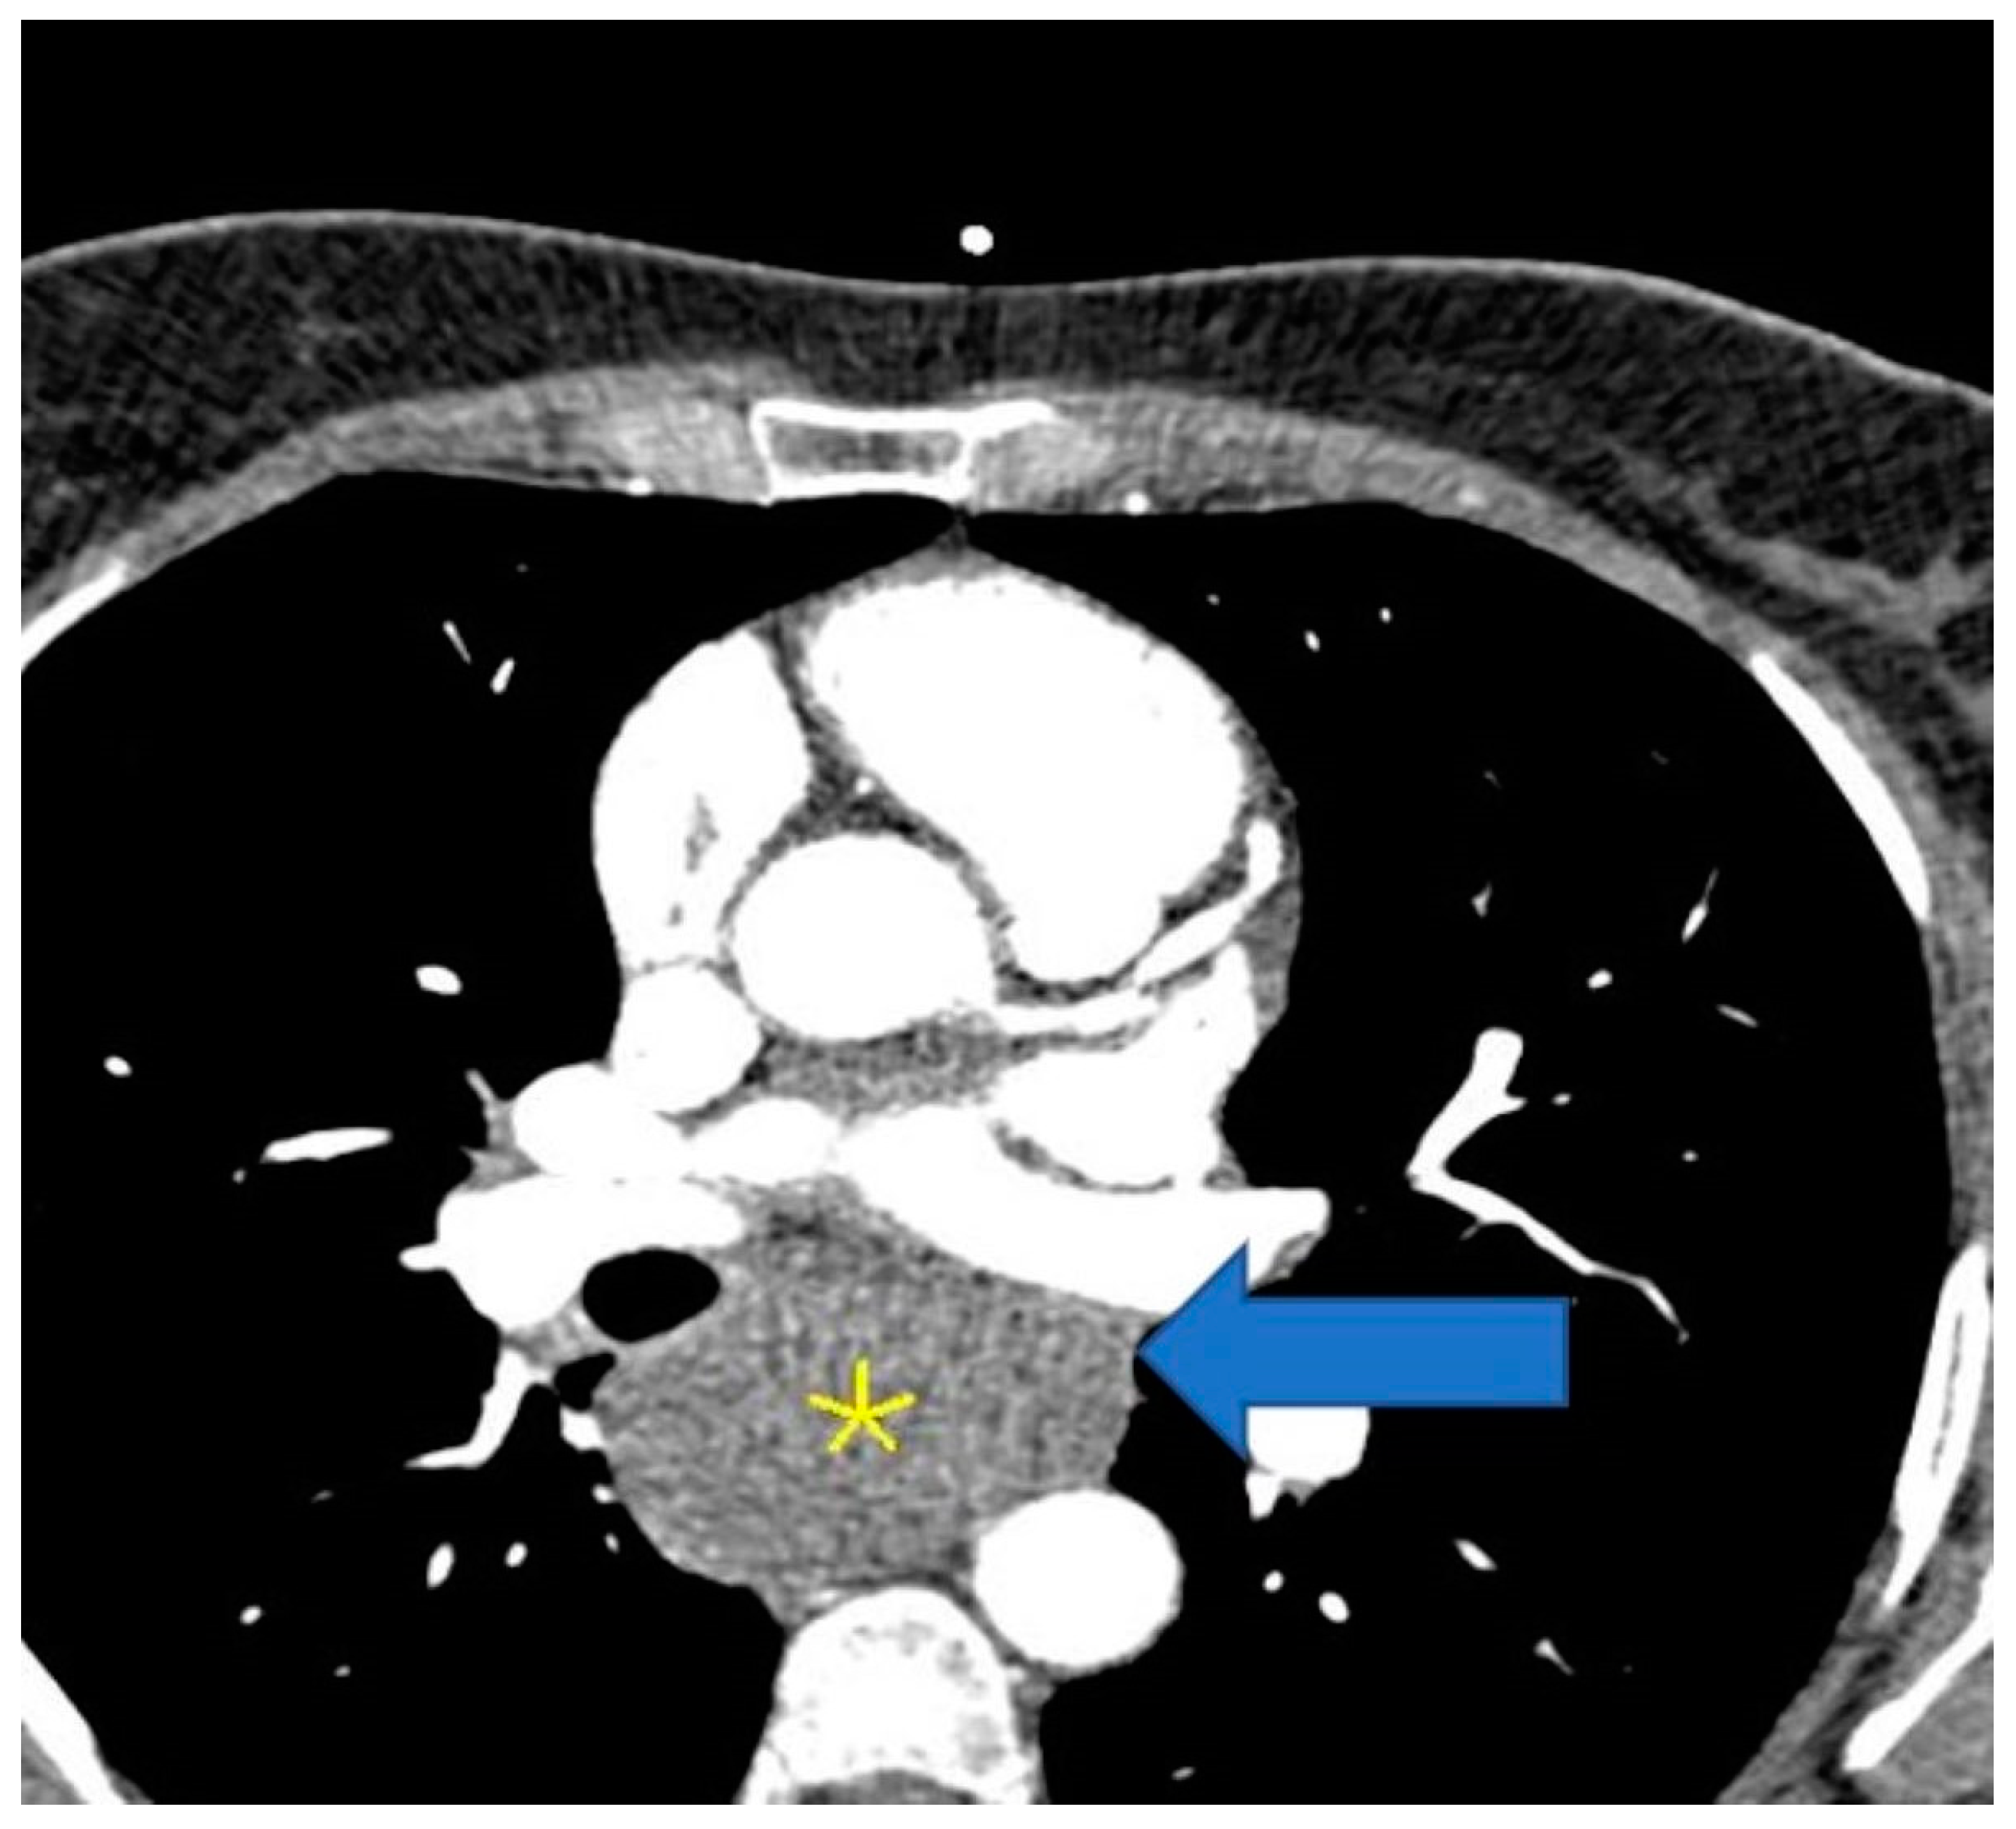

The patient was referred to the radiology department for computed tomography (CT) angio-coronarography, which revealed a voluminous mass situated into the mediastinum oriented towards and beneath, encompassing the esophagus and compressing it. The described mass measured 57 mm in diameter and was in direct contact with the carinal. Internal densities of 71 HU ruled out the presence of lipoma or mediastinal cyst, suggesting an esophageal mass or (less likely) fused lymph node block. The total Ca score was 7.7 UA and there was a single calcific spot in the middle segment of the right coronary artery (RCA), with no significant predictive risk for acute coronary events. The heart was predominantly supplied by the RCA, with the normal origin and initial course of the coronary arteries. There was dominant RCA, patent, with a single 2 mm calcific spot in the middle segment, no significant stenosis, and patent otherwise. The left main (LM) is bifurcated and patent. Left anterior descending (LAD) and diagonals were without atheromatosis, with no stenosis or occlusions. The left circumflex coronary artery (LCX) was patent. The aortic valve was tricuspid aortic, with normal function. Internal mammary arteries, pulmonary arteries, and veins were normal, without thrombosis or abnormal drainage. Ascending aorta had normal diameter and flow, without any pathological changes in the left ventricular myocardium or the left cardiac chambers on computed tomography (Figure 5 and Figure 6).

Figure 5. CT thorax with contrast (for coronary angiography) showing a solid mass enveloping the esophagus (yellow star).